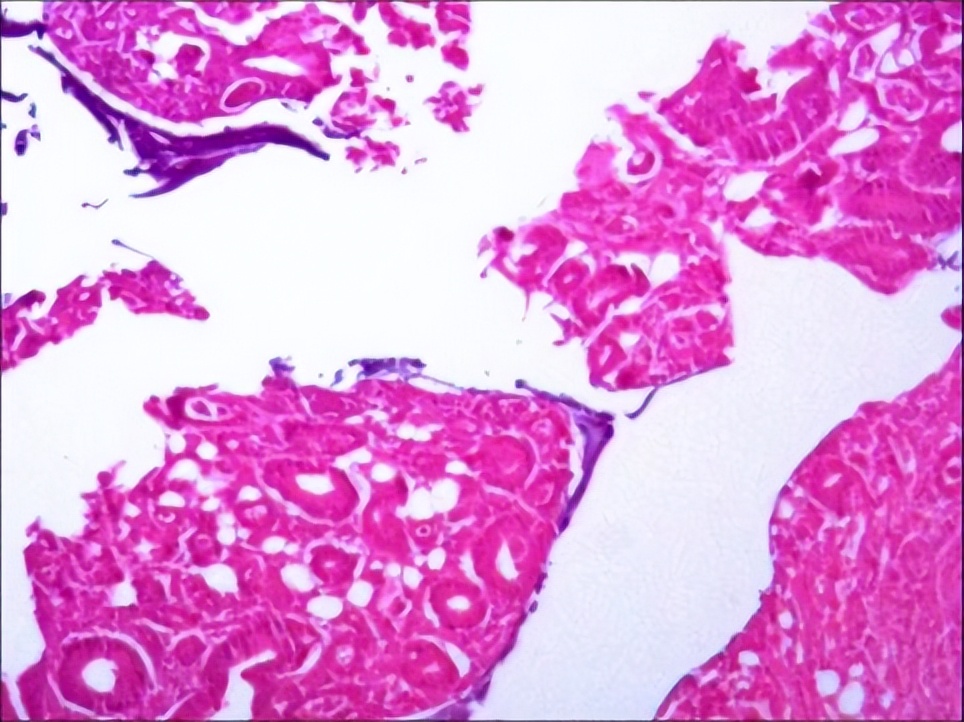

2017.11术后病理

1.(左肝外叶)结合HE形态及临床病史,符合肝转移性腺癌伴灶区坏死(肠癌 原发),送检标本之断端未见癌累及。2.(胆囊)慢性胆囊炎,切片未见癌累及。3.(吻合口原发肿物)肠中分化腺癌(肿物大小:4x3x1.5),癌组织浸及肠壁全层,切片未见明显神经及脉管浸犯;另于肠系膜检出淋巴结9枚,其中2枚见癌转移(2/9)。

▲肝脏病理。

▲吻合口原发肿物病理。